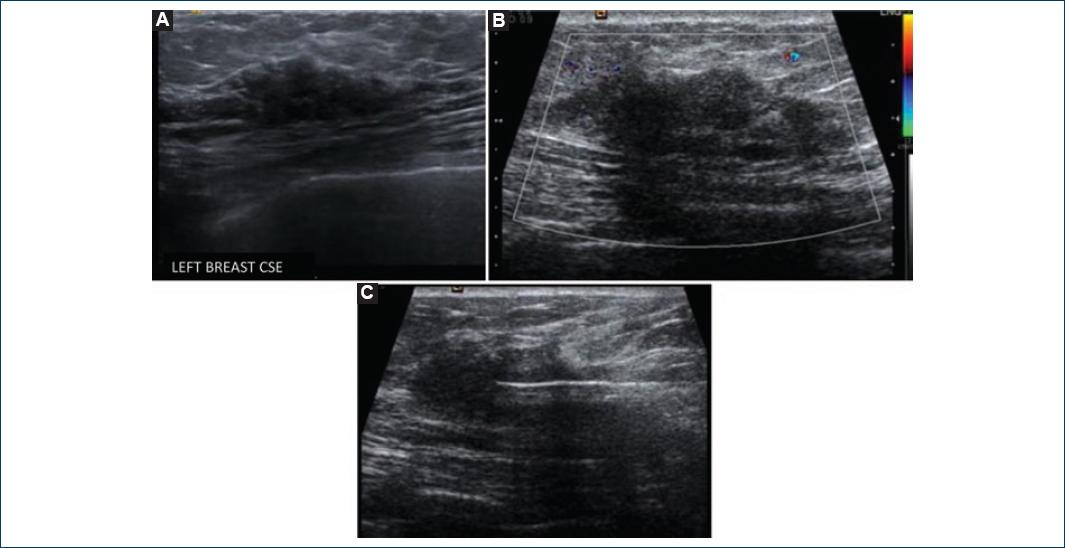

37-year-old woman, with a long history of T1DM, has been diagnosed with multiple diabetes-related complications such as chronic kidney disease, retinopathy, and hypertension. The chief complaint included a 2-week history of an enlarging left breast lump. Clinical examination showed a 5-cm left breast nodule and no enlarged nodes where detected during axillary examination. Mastography and mammary ultrasound showed BI-RADS 4c (Fig. 1). Ultrasound-guided biopsy was performed, and pathology study showed DM without evidence of invasive carcinoma (Fig. 2).

Figure 1 Breast ultrasound. A: irregular mass with angular margin and parallel orientation, show posterior shadowing. Color Doppler showing no vascular flow within the mass; B: percutaneous breast biopsy and the tip of the needle lie in the center of the lesion.